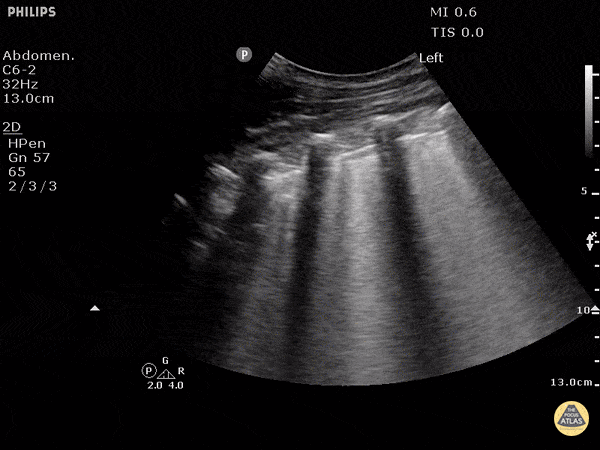

POCUS for the case found here:

(POCUS Source: http://www.thepocusatlas.com/pulmonary)